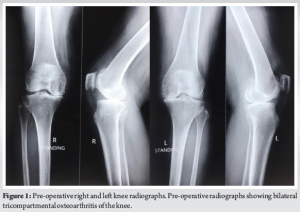

An 80-year-old female presented to our outpatient department with bilaterally painful knees, diagnosed to have bilateral tricompartmental knee osteoarthritis (Fig. 1 and 2) without any comorbidities. The patient was operated for bilateral TKR in staggered manner 2 weeks apart with the left side being operated first. Both the knees were operated with Zimmer-Biomet CR vanguard prosthesis with 10 mm polyethylene insert being used on both the sides (Fig. 3 and 4). The post-operative course was uneventful with patient achieving full range of motion (ROM) 0–120°. The follow-up of the patient at 3 and 6 months was unremarkable as well, with patient being able to carry out her daily activities unassisted.